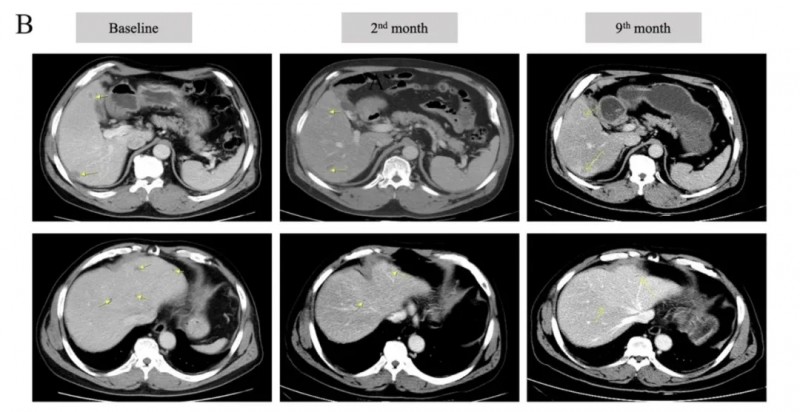

结果显示:经过四次注射,患者的CEA水平从初始126.7ng/mL降至82.73ng/mL(详见下图A)。腹部增强CT图像显示,治疗期间多个肝脏占位性病变均有不同程度缩小甚至消失(详见下图B)。

▲图源“Cancer Immunol Immunother”,版权归原作者所有,如无意中侵犯了知识产权,请联系我们删除